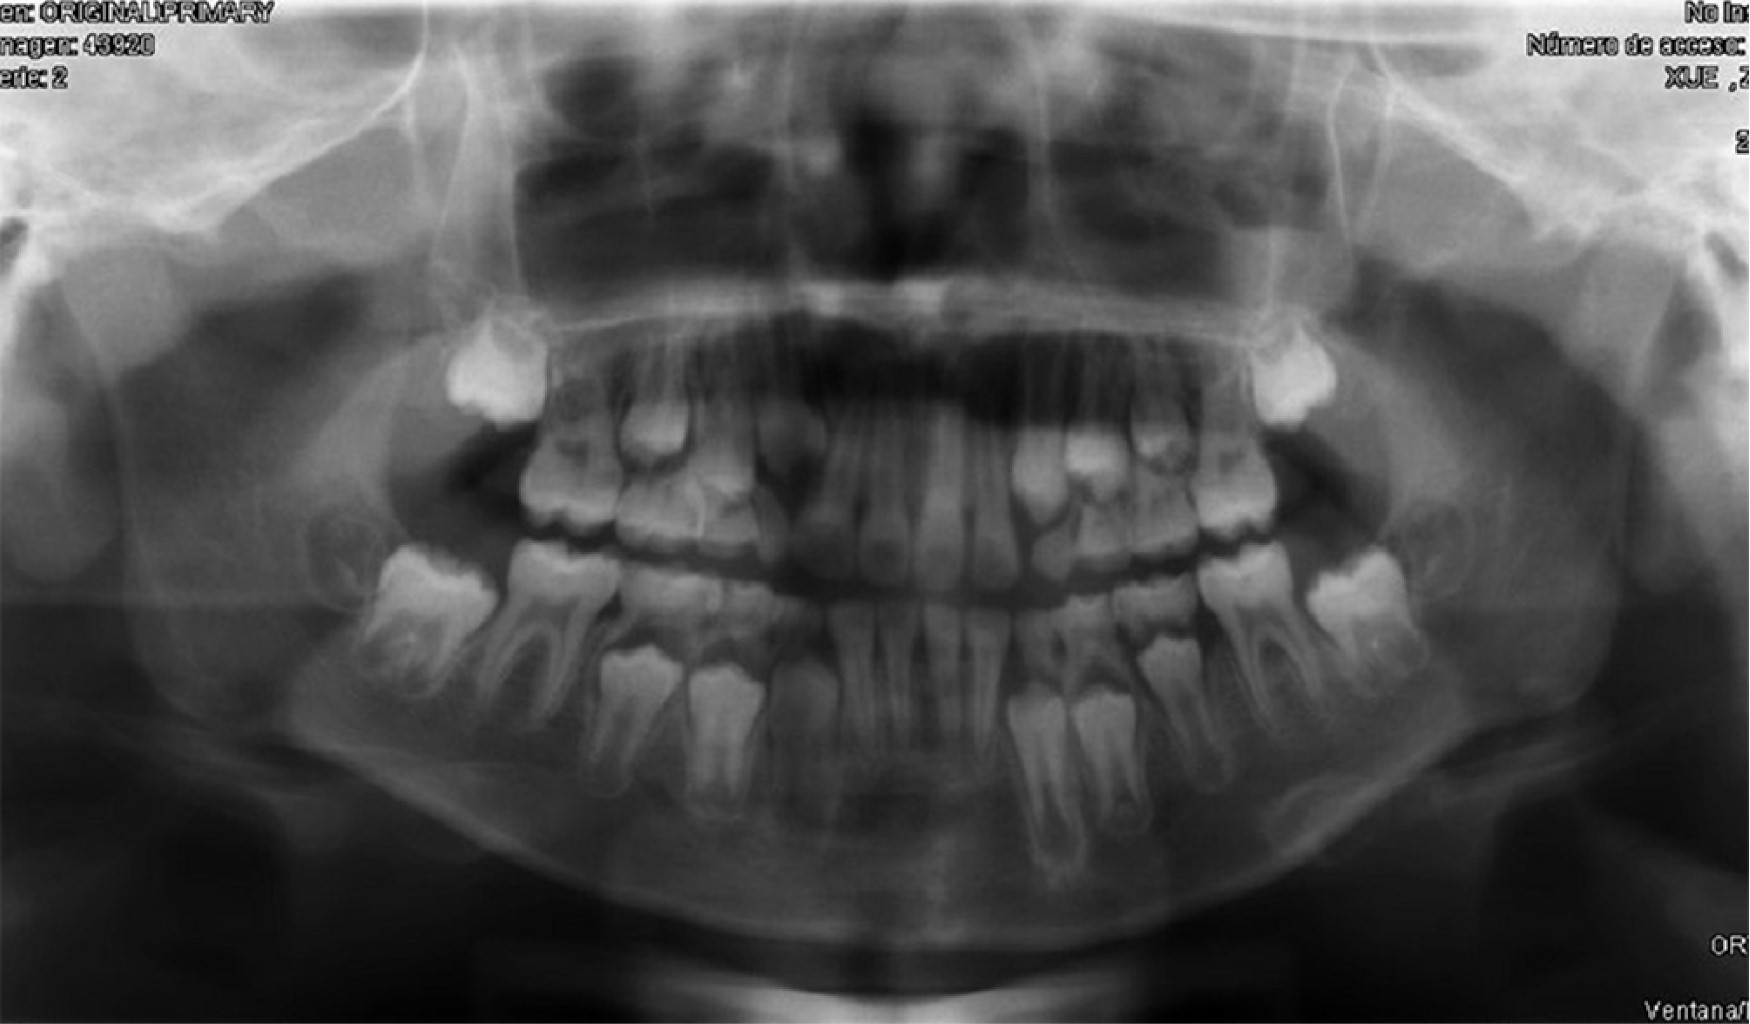

Introduction: Oral cavity squamous cell carcinoma is a frequent entity in adult malignant head and neck pathology; however, it is extremely rare in pediatric age. The treatment and reconstruction of pediatric patients is a challenge due to its high complexity and the few cases described to date in the literature. Material and methods: A clinical case of mandibular squamous cell carcinoma in a pediatric patient is presented. Diagnosis is made by histopathological study and radiological tests, and a virtual planning for mandibular reconstruction is performed. A review of the literature is performed since it is a rare entity. Results: A 9-year-old male of Asian origin came to our office for clinical symptoms of suppuration in the left mandibular region close to the first definitive molar, of approximately 2 months of evolution. A biopsy was performed with an anatomopathological result of squamous cell carcinoma. The case was presented to the Head and Neck Tumors Committee and surgical treatment was decided: left segmental mandibulectomy with oncologic safety margins, left anterolateral functional cervical dissection and reconstruction with microvascularized fibula flap fixed with titanium rod. Cutting guides and virtual planning were used. At 24 months postoperative follow-up there was no locoregional or distant recurrence. Conclusions: Oral cavity squamous cell carcinoma in pediatric age has a low incidence, requiring optimal management and reconstruction. The fibula flap could be the most indicated option for mandibular reconstruction in children. The preservation of the mandibular condyle could favor the mandibular growth of the patient during development.

Figure 1